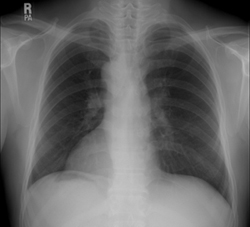

Routine ECG(Fig. 1) and simple chest X-ray(Fig. 2) were recorded. She was diagnosed as "situs inversus" finally.

Fig 2.

Simple chest X-ray showed dextrocardia, long hypoarterial right main bronchus, left sided large lobe of liver and right sided stomach gas.